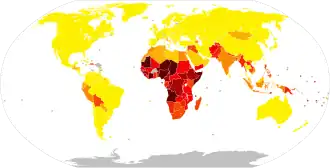

An estimated 16.3 million people worldwide were infected in 2015.[8] Most cases occur in the developing world, and people of all ages may be affected.[6][17] In 2015, pertussis resulted in 58,700 deaths – down from 138,000 deaths in 1990.[9][18] Outbreaks of the disease were first described in the 16th century.[11] The bacterium that causes the infection was discovered in 1906.[11] The pertussis vaccine became available in the 1940s.[11]

Pertussis is endemic worldwide. More than 151,000 cases were reported globally in 2018.[12] However not all cases are reported or correctly diagnosed, especially in developing countries. Pertussis is one of the leading causes of vaccine-preventable deaths worldwide.[55] A study in 2017 estimated the global burden of the disease to be 24 million cases per year with 160,000 deaths among young children, with about 90% of all cases occurring in developing countries.[56][55]